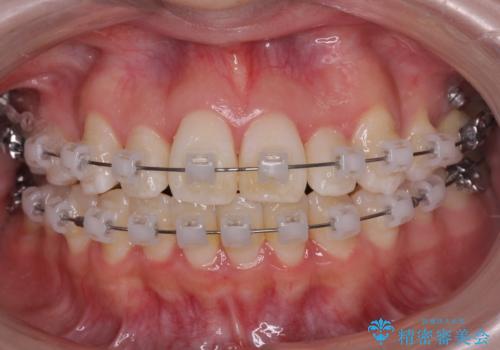

治療は3年以上かかりそうと説明しましたが、2年台で終わらせることができました。

上下左右4本抜歯の可能性を説明していましたが、実際は上顎2本の小臼歯抜歯で済みました。

矯正用インプラントを使用して治療しています。

上下の顎の幅もあっておらず、成人でしたが手術なしで上あごを骨から広げる処置(急速拡大装置)を行いました。